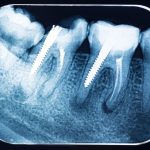

El Dolor de Muelas: Principales Causas y Síntomas

El dolor de muelas es una experiencia desagradable que muchas personas han experimentado en algún momento de sus vidas. Este dolor puede variar en intensidad, desde una molestia leve hasta un dolor agudo y punzante. Se origina en la zona de la boca y puede afectar tanto a los dientes como a las encías circundantes. Comprender las causas y los síntomas del dolor de muelas es esencial para abordar este problema de manera efectiva.

- Caries Dental: La caries es una de las causas más comunes de dolor de muelas. Ocurre cuando las bacterias presentes en la boca producen ácidos que corroen el esmalte dental, creando cavidades que pueden exponer los nervios sensibles del diente.

- Infección Dental: Una infección en el diente o en las encías puede causar inflamación y dolor. La acumulación de bacterias en una cavidad dental no tratada puede llevar a una infección dolorosa conocida como absceso dental.

- Muelas del Juicio: La erupción de las muelas del juicio puede causar dolor debido a la falta de espacio en la boca. Pueden quedar impactadas o parcialmente erupcionadas, lo que provoca incomodidad.